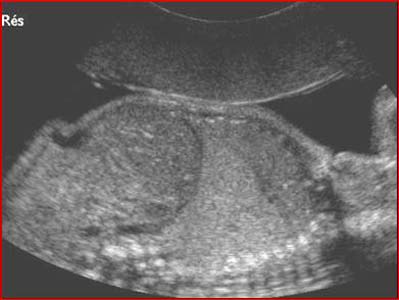

Masse hyperéchogène dans le base pulmonaire